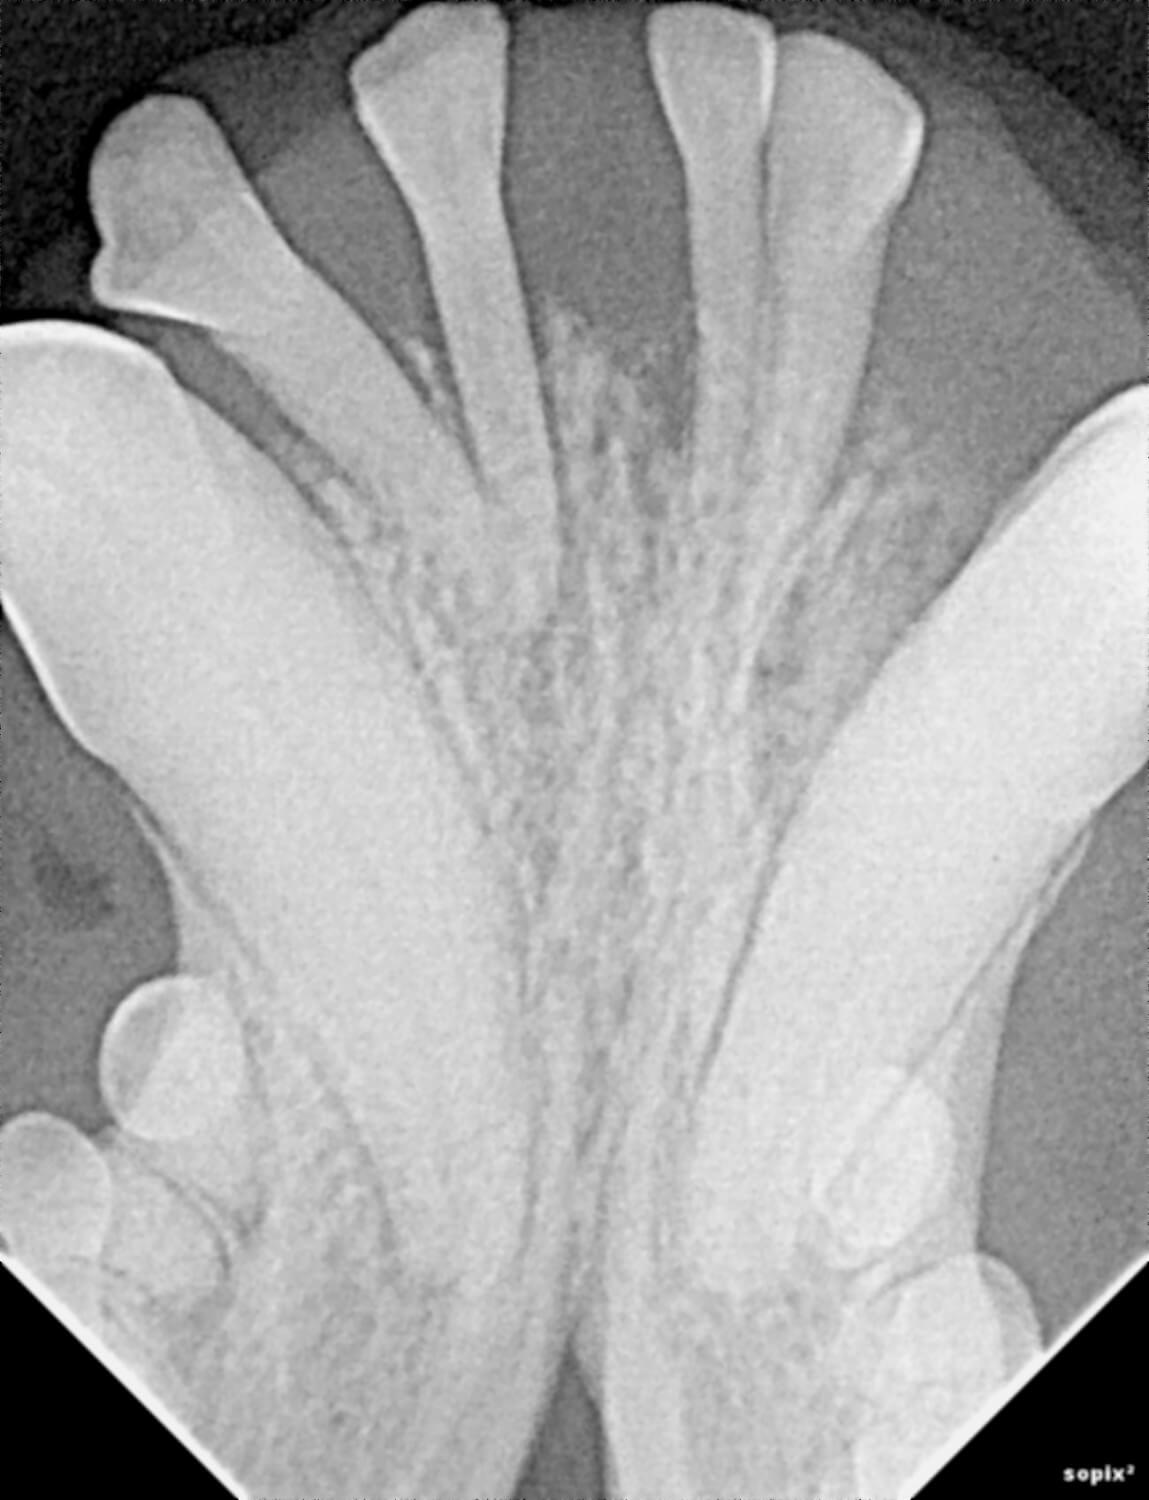

Digital radiology is a state-of-the-art imaging technique used to produce highly detailed X-ray images of your pet’s teeth, mouth, and jaw. This technology replaces traditional film X-rays; it provides instant results and clearer images, which lead to faster, more accurate diagnoses.

Our veterinarians use digital radiology to detect conditions such as tooth root abscesses, oral tumors, jaw fractures and hidden dental and periodontal issues. Early diagnosis enables timely treatment, reducing pain and preventing advanced dental complications.

We utilize state-of-the-art digital X-ray equipment to capture detailed images in seconds. The images appear instantly on our monitors, allowing our veterinarians to review and interpret results right away. This technology reduces your pet’s radiation exposure compared to traditional film.

Digital radiology plays a vital role in preventive health and advanced diagnosis for pets. Dental and oral conditions are often hidden below the gumline, where physical exams cannot detect them.

This imaging can reveal issues such as periodontal disease, infections, tooth resorption, and bone loss before they cause noticeable pain or lasting damage. Prompt diagnosis allows our team to provide targeted treatments that keep your pet comfortable and healthy.

Precise imaging guides our veterinarians in planning surgical or dental procedures for maximum safety and effectiveness. Detailed X-rays also support ongoing monitoring for chronic conditions.